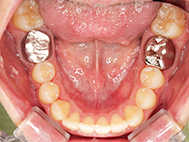

Before

| 症状 | 上顎前歯部叢生 |

上の前歯がハの字隣の歯が引っ込んでいる

前歯のガタガタが気になるとの事で来院されました。

装着が目立ちたくないとの事でアライナ-での矯正を希望されました、歯の間を削り少し歯の幅をスリムにして綺麗なアーチに並びました。